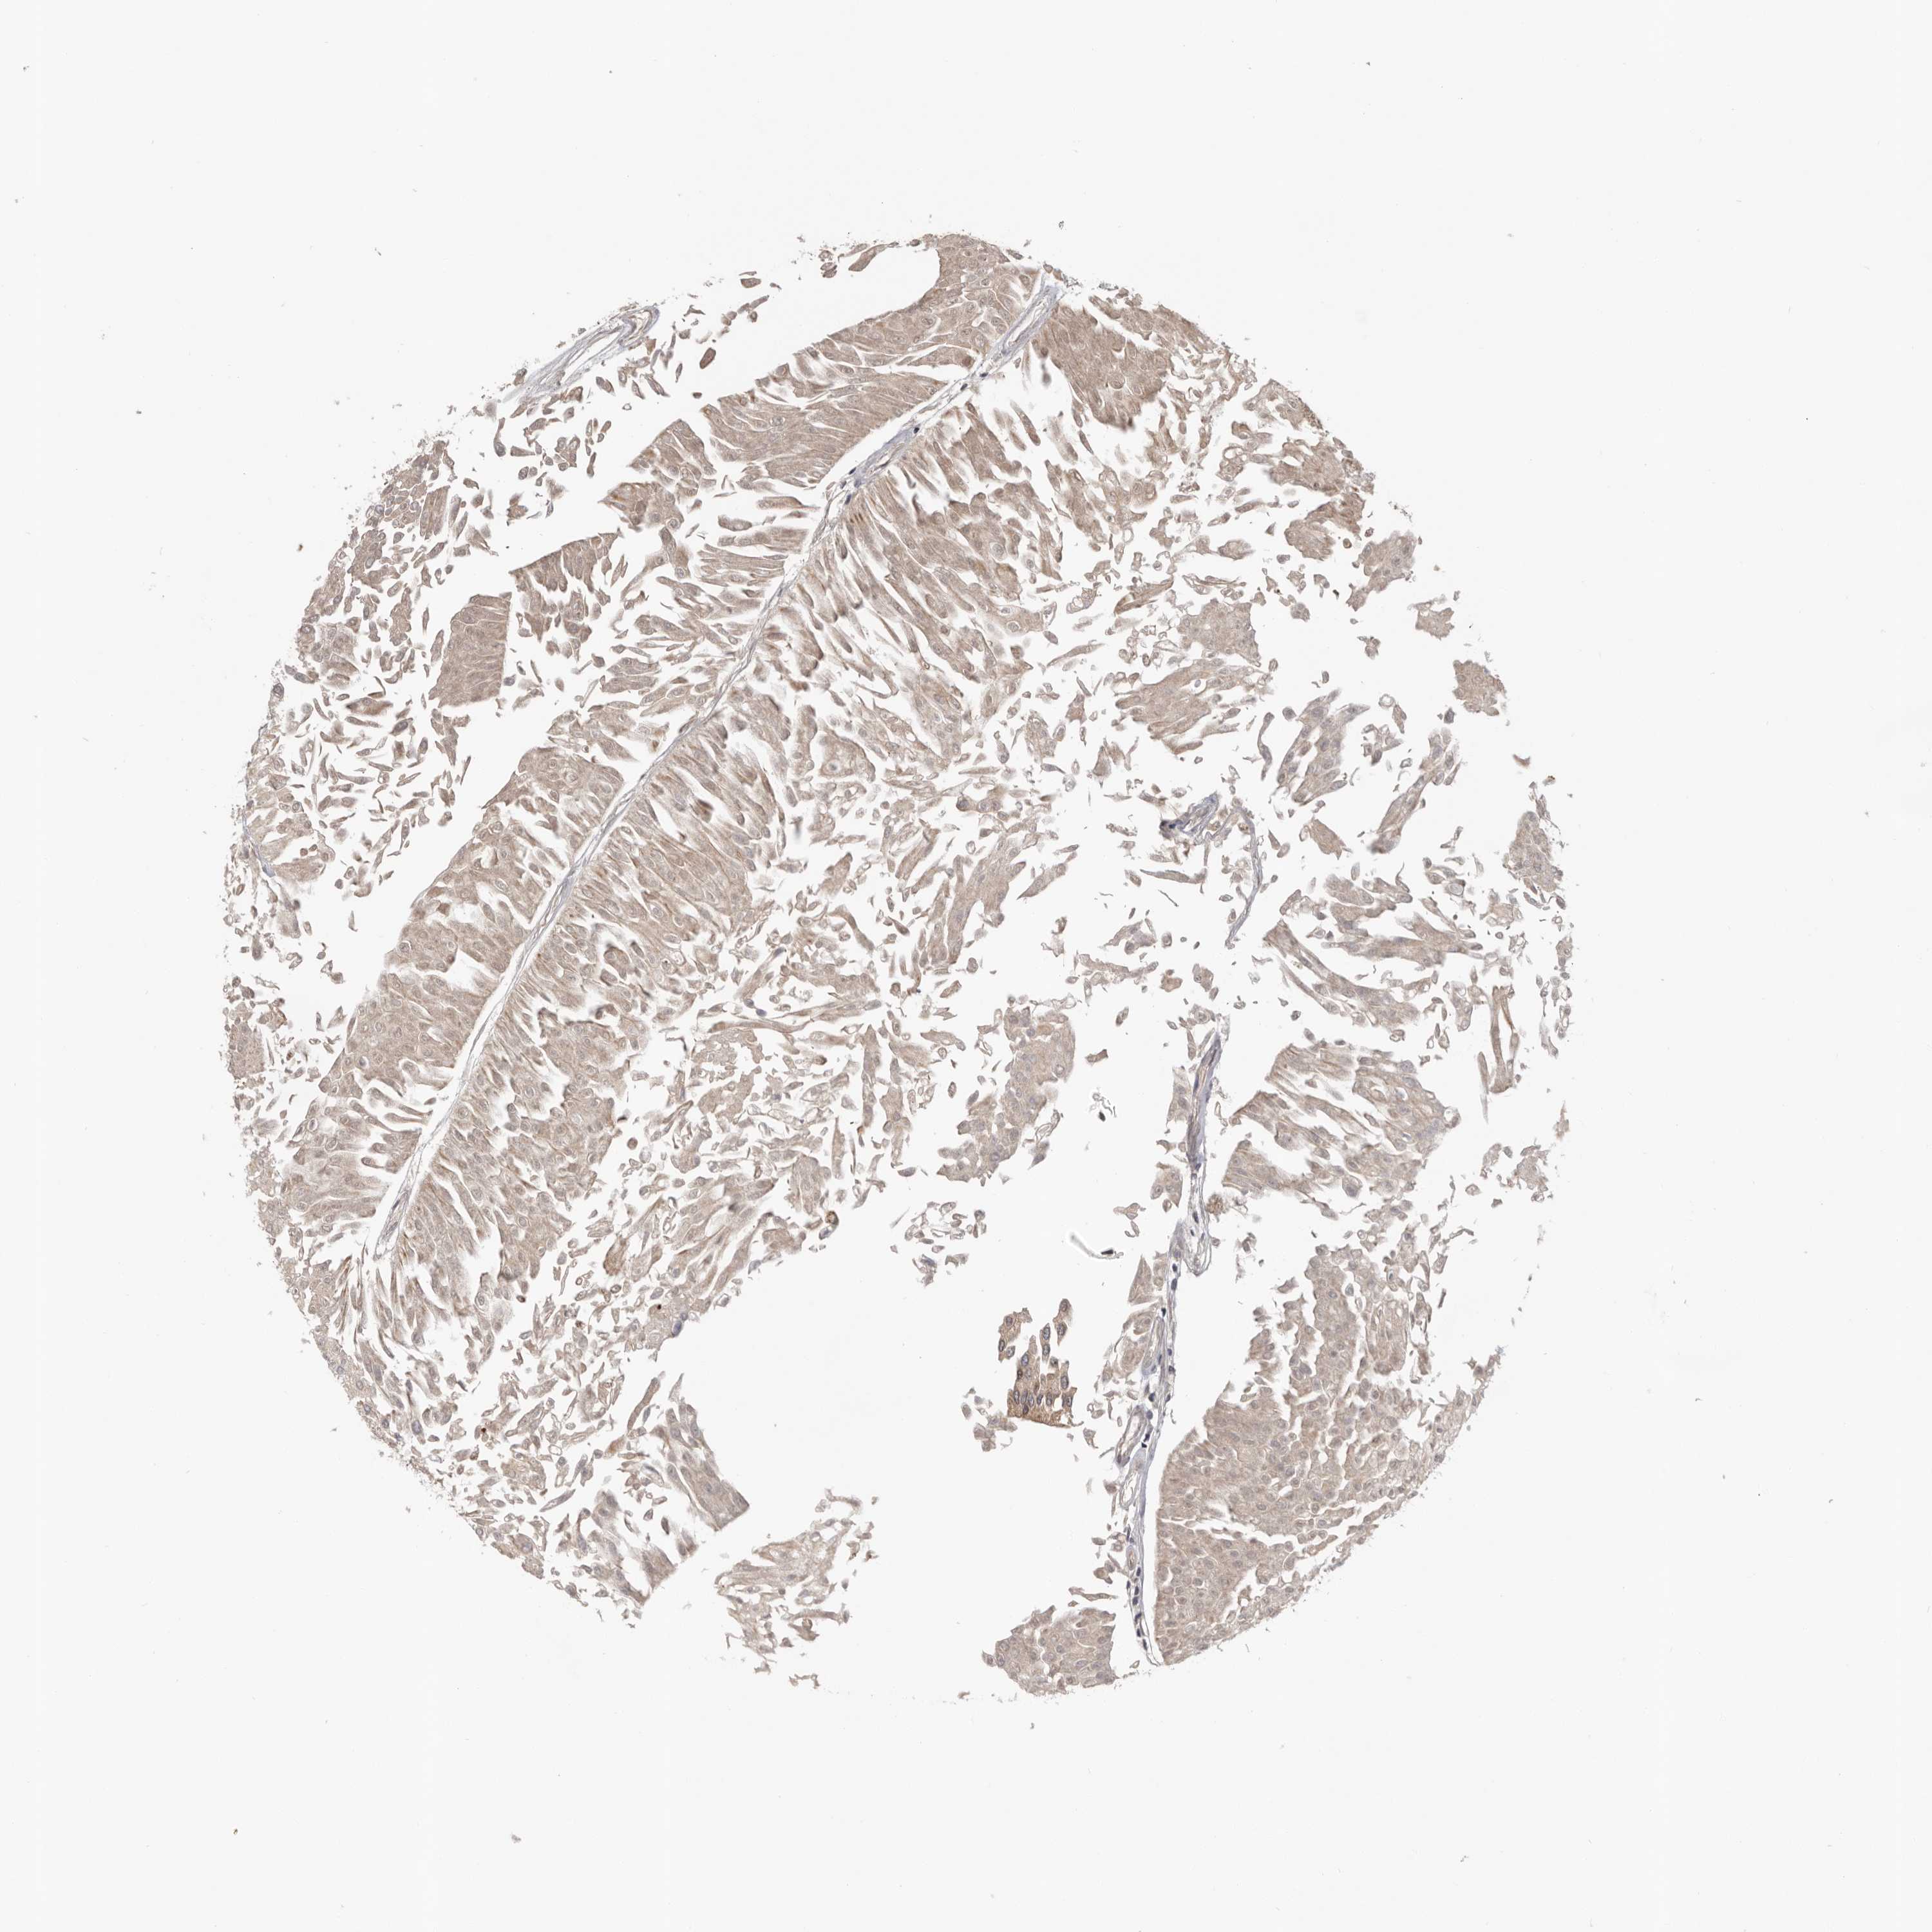

UROTHELIAL CANCER - Protein expressioni

A mouse-over function shows sample information and annotation data. Click on an image to view it in a full screen mode. Samples can be filtered based on level of antibody staining by selecting one or several of the following categories: high, medium, low and not detected. The assay and annotation is described here.

Note that samples used for immunohistochemistry by the Human Protein Atlas do not correspond to samples in the TCGA dataset.

Antibody stainingi

Antibody staining in the annotated cell types in the current human tissue is reported as not detected, low, medium, or high, based on conventional immunohistochemistry profiling in selected tissues. This score is based on the combination of the staining intensity and fraction of stained cells.

Each image is clickable and will lead to virtual microscopy that enables deeper exploration of all samples and also displays staining intensity scores, fraction scores and subcellular localization as well as patient and tissue information for each sample.

Antibody HPA024313

Antibody HPA027983

Antibody HPA028628

Urothelial carcinoma, Low grade

Urothelial carcinoma, High grade